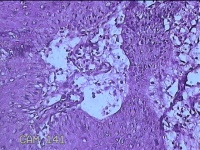

下唇肿物

性别

女

年龄

9岁

临床诊断

唇粘液囊肿

一般病史

下唇肿物1月

标本名称

大体所见

灰白暗红色肿物0.8x0.5x0.2cm一个,表面糜烂。